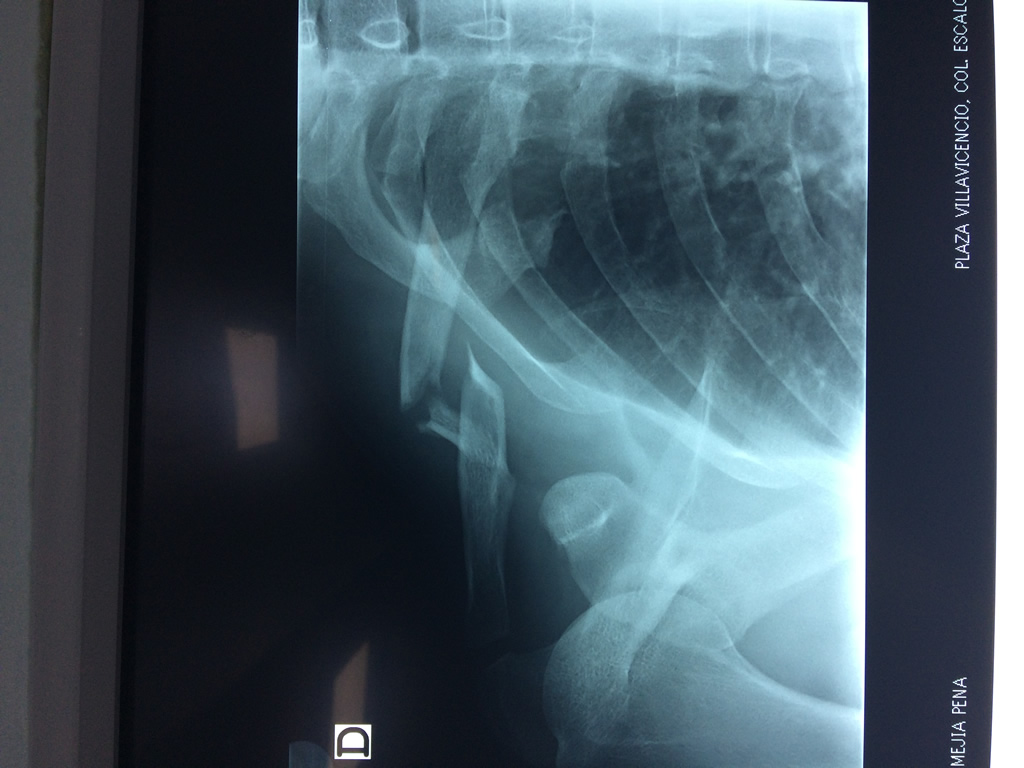

Cirugías de Codos - Clavícula

La clavícula es un hueso largo, con forma de "S" itálica, situado en la parte anterosuperior del tórax. Junto con la escápula forman la cintura escapular. Se puede palpar por toda su longitud y se extiende del esternón al acromion de la escápula, siguiendo una dirección oblicua lateral y posterior.